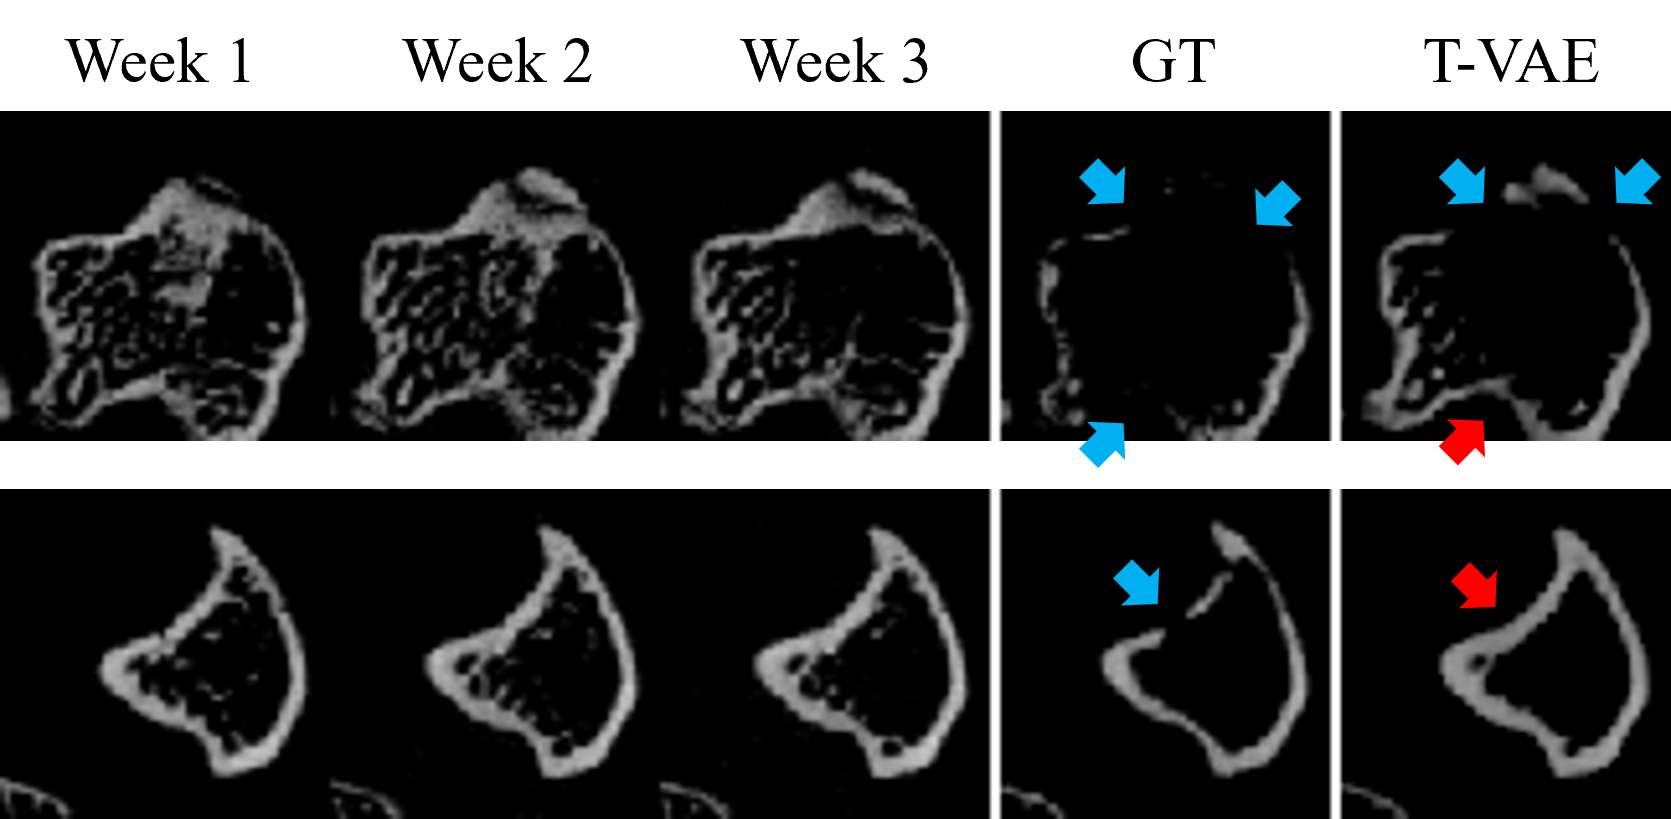

Refer to caption

Figure 5: Failure samples generated by our method. In each row, we show the slices of the first three weeks, the ground-truth slice in week 4, and our predicted slice. Red arrows indicate wrong lesion predictions. Blue arrows indicate lesions in the ground-truth image or correct lesion predictions.

2.6 Failure Cases

Figure 5 shows two cases where our model does not make very accurate predictions. In the first row, our model is able to predict two of the lesions but fails to predict all the lesions. In the second row, our model fails to predict the lesion. In summary, our model sometimes cannot predict the lesion in a very accurate way when the lesion occurs in the fourth week but there is no lesion in the first three weeks. We will address these challenging cases in our future work.